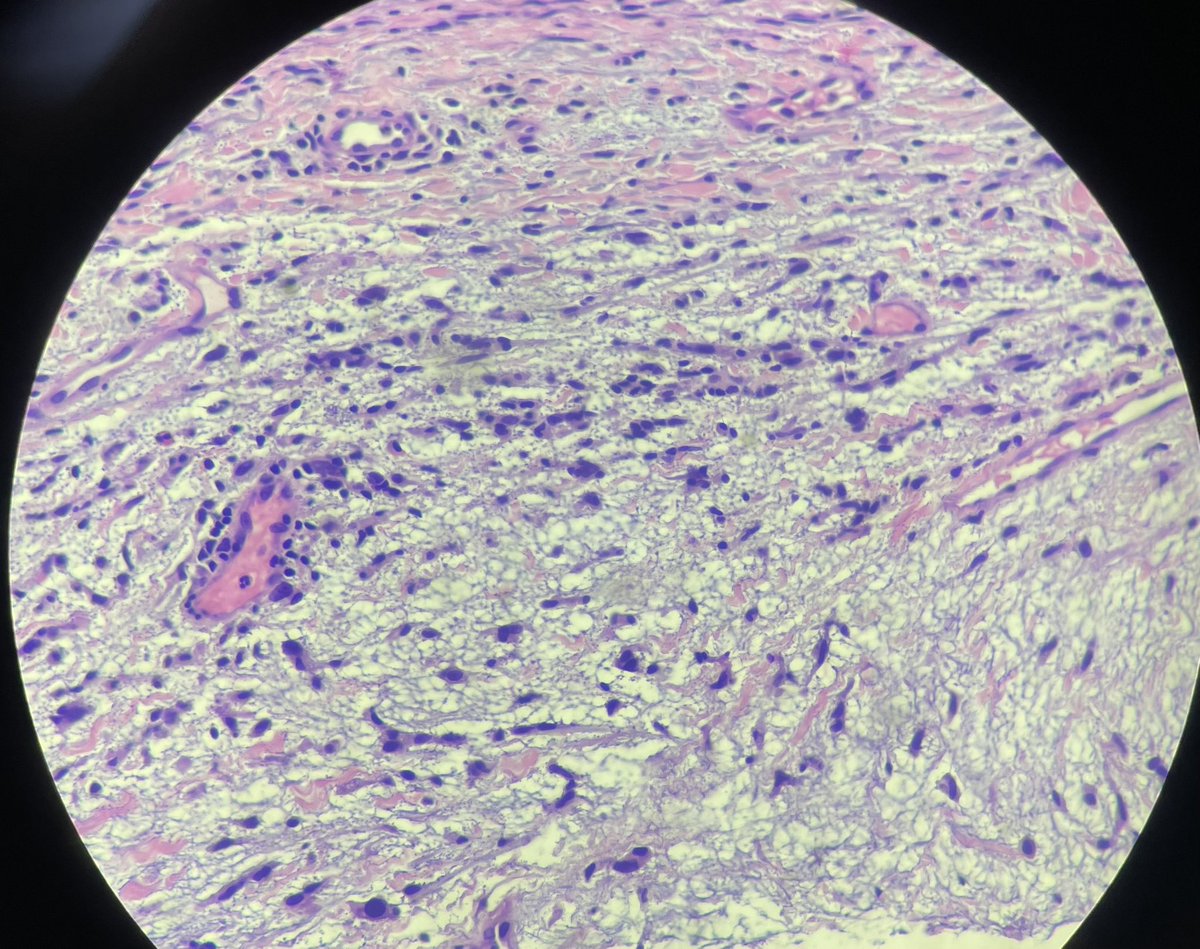

Calf. Elderly. Dx’s welcomed.

@tonitatirado @mccalmo @HENRYY_MD F13a and cd163 in order. @HENRYY_MD, are you the man now? Not perfect but??

Thanks all (@tonitatirado @mccalmo and @HENRYY_MD). Added some more IHC (cd168, F13a, pankeratin) that are probably low yield but odd lesion. Still think it’s focal mucinosis.

>70yo thigh. Eryrhematous nodule with hyperkeratotic scale. @mccalmo @HENRYY_MD Neg for CD34, sox10, cd30 (cd30 bc history said LyP, later found out it’s an autopopulate error). Focal cutaneous mucinosis? Cells are odd though.